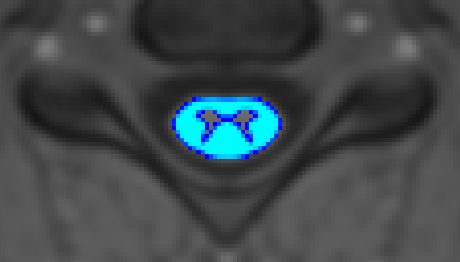

Question 3.

This sample image is of the MT data, right? (I ask because the screenshot is captioned sct_register_multimodal - MT, so I wanted to make sure.)

If so, then I think there is at least enough detail here to try segmenting the GM seg. From there, this GM seg could be used create a WM seg, which could then inform the template registration, via the steps in the Segmenting the gray and white matter and Improving registration results using white and gray matter segmentations tutorials.

Note: SCT has a new contrast-agnostic gray matter model (sct_deepseg graymatter), and so you may wish to substitute in this model for the existing sct_deepseg_gm step in the first tutorial above. We are currently in progress for updating the documentation! :slight_smile:

WM-informed template registration allows you to largely keep the registration the same (due to the same SC segmentation used as the outer boundary for -iseg and -dseg), while also slightly tweaking the registration to match the inner boundary of the GM. This may result in more accurate registration / atlas warping, and the end result may be improved even if the GM segmentation alone was not sufficient for computing metrics.

not a question of noise but of contrast-- based on your 3rd PNG contrast seems ok-- did you try the latest GM seg model? regardless you’ll need information about disc level